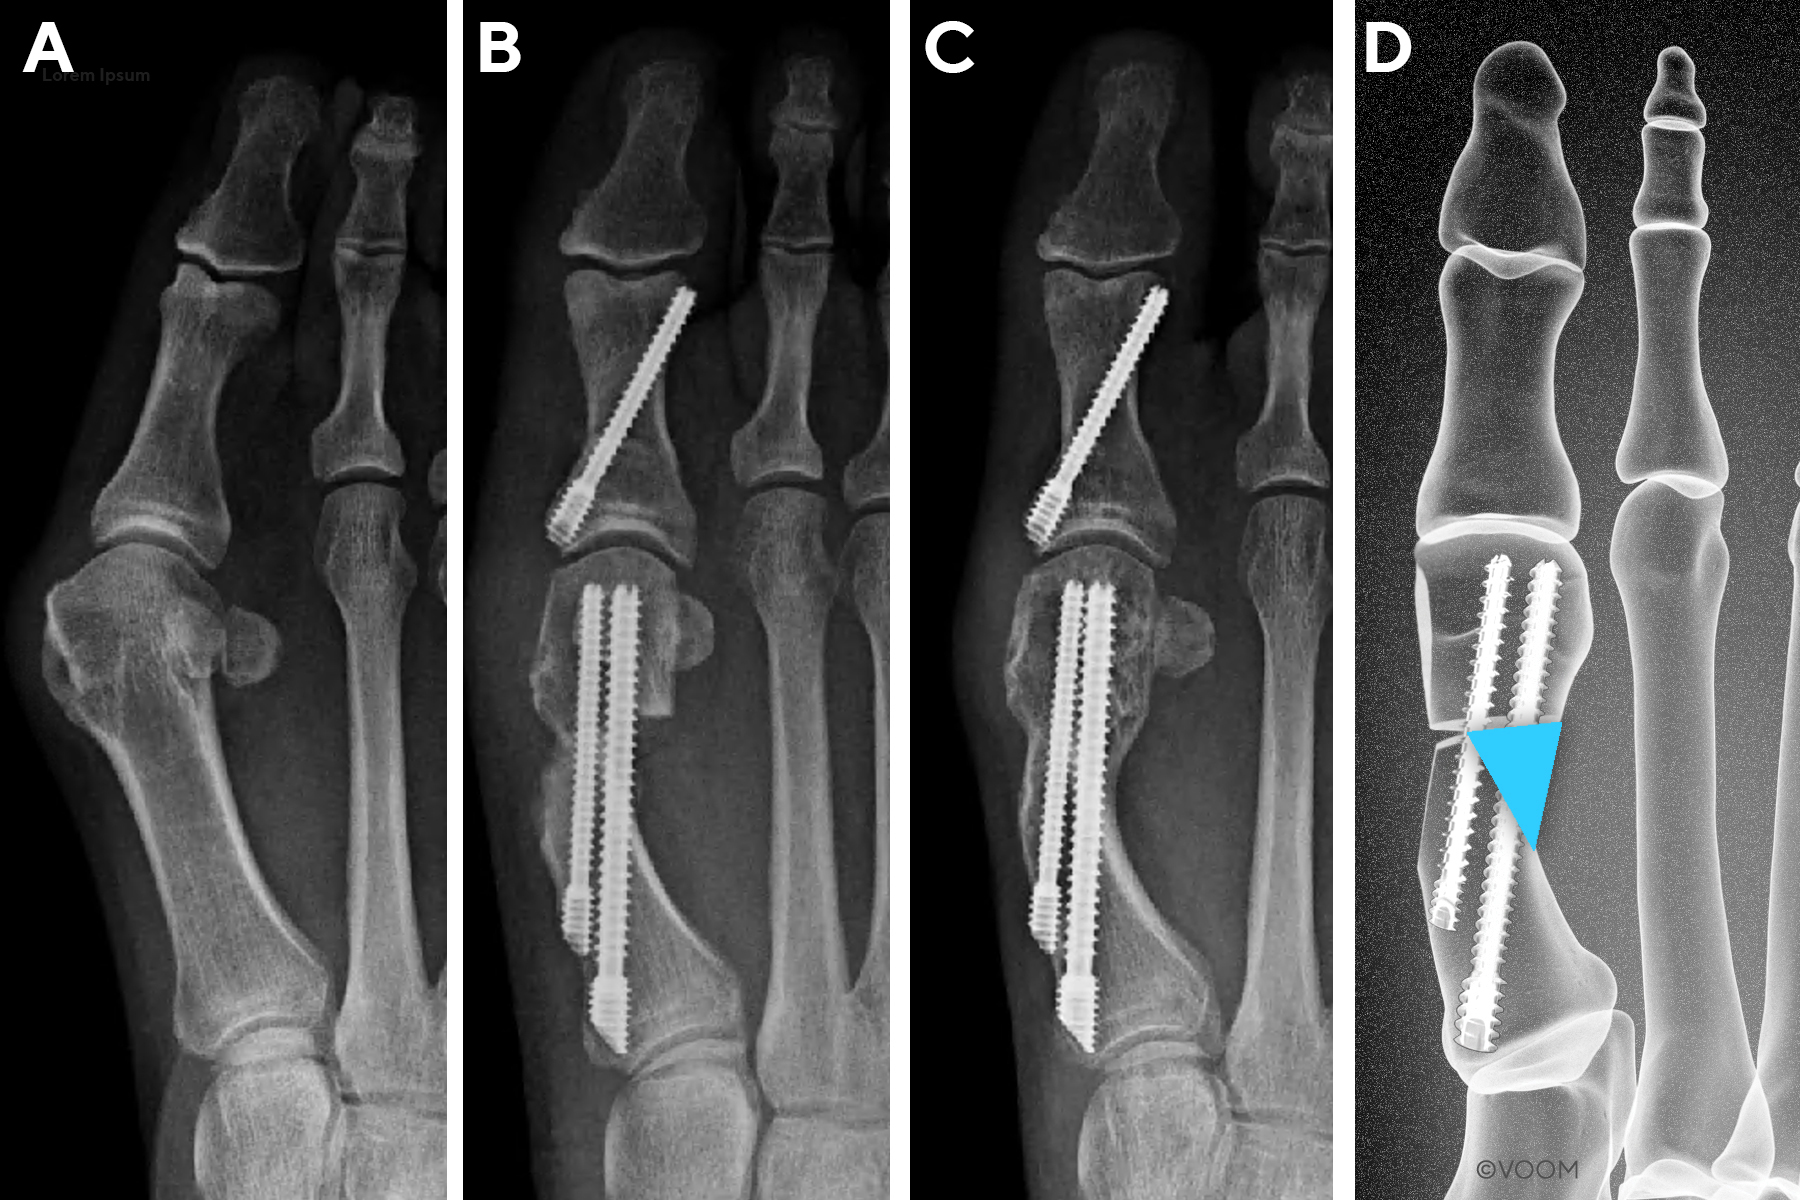

First Metatarsal Regeneration Type III: Robust callus formation with first metatarsal regeneration (Figure 4).

_type_iii.jpg)